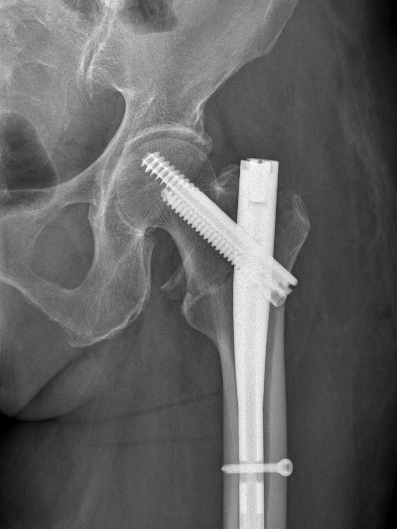

2025年11月1日,由遵义市医学会手外科分会主办、遵义市第二城市医疗集团(贵州航天医院)承办的遵义市医学会手外科分会学术交流会暨贵州省继续医学教育项目《急诊手外伤治疗临床研究新进展专题研讨班》在贵州航天医院成功举办,汇聚了遵义市手外科领域专家及基层医疗骨干,通过专题研讨与临床经验分享,共探急诊手外伤诊疗新进展。 会议特邀遵义市医学会手外科分会主任委员金文虎教授,遵义市医学会手外科分会副主任委员张子阳教授,遵义市医学会手外科分会常务委员杨绍浦教授,贵州航天医院陈明勇教授、赵兴东教授等遵义市手外伤专家进行交流分享;贵州航天医院党委委员、副院长彭亮参加会议并致辞,贵州航天医院骨科医务人员,遵义市第二城市医疗集团成员单位及红花岗区、绥阳县、桐梓县等区县医疗机构手外伤骨干参与。 贵州航天医院党委委员、副院长彭亮致辞 学术交流 本次学术交流以“急诊手外伤治疗临床研究新进展”为主题,通过理论授课与临床案例结合,共同探讨急诊手外伤临床诊疗全链条诊疗策略、关键技术、临床研究新进展,促进规范化诊疗技术向基层下沉,助力提升区域手外伤应急处置与修复能力。 贵州航天医院赵兴东教授分享《急诊手外伤的诊断与治疗原则》 贵州航天医院陈明勇教授分享《开放性骨折的治疗原则》 贵州航天医院张军教授分享《甲沟炎Winograd手术的临床应用》 贵州航天医院赵兴东教授分享《手部常见的皮肤缺损及治疗原则》 贵州航天医院张艳金教授分享《开放性骨折的清创术》 贵州航天医院冷家雄教授分享《下肢创面修复的常用皮瓣之股前外侧皮瓣》 贵州航天医院邬夏荣教授分享《踝关节慢性不稳的诊治》 贵州航天医院卢懿明教授分享《掌骨骨折》 贵州航天医院张艳金教授分享《手部肌腱的解剖与修复方法》 本次研讨班为遵义市手外科领域医务人员提供了深度交流契机,强化了医疗机构间的协作网络,进一步推动学科创新与临床实践融合,为健康遵义建设注入新动能。 贵州航天医院骨科专家简介 陈明勇 骨一科主任,副主任医师 临床擅长:从事创伤骨科工作约20年,对骨缺损、骨不连、骨肿瘤、肢体畸形等的肢体矫形重建及功能重建,慢性化脓性骨髓炎的根治治疗、糖尿病足的保肢治疗、快速康复理念(ERAS)下的老年骨折的诊治,四肢复杂骨折的诊治,四肢骨折等微创手术治疗具有丰富的临床经验。 2004年毕业于遵义医学院临床专业,曾在中国人民解放军总医院、广西医科大学第一附属医院、上海第六人民医院骨科进修。中国中西医结合学会骨伤科专业委员会横向骨搬移治疗糖尿病足及微血管网再生学组首届委员,遵义市医学会创伤分会常务委员。 瞿 晖 骨科党支部书记,骨二科主任,副主任医师 临床擅长:对骨科的常见病、关节外科、脊柱外科及运动医学疾病的诊治具有丰富的临床经验,熟练掌握骨科手术操作技术。 毕业于遵义医学院临床医学系,2005年前往广州中山大学第一附院骨显微医学部进修学习,2011年前往成都华西医院进修学习,并多次在省内外学习骨科相关知识,是中华医学会骨科分会会员。 赵小锋 中共党员,骨二科副主任,副主任医师 临床擅长:从事骨科临床工作11年,对骨科常见病、多发病诊疗有较为丰富的临床经验,擅长脊柱相关疾病诊断及治疗,尤其是颈、腰、腿疼痛疾病诊断及治疗,擅长胸腰椎骨折微创经皮穿刺内固定术、经皮穿刺椎体成形术、经皮穿刺脊柱内镜下腰椎间盘摘除术、单纯开创腰椎间盘摘除术、腰椎滑脱复位椎间植骨椎融合内固定术、腰椎管狭窄减压融合内固定术及人工髋、膝关节置换术等。 2012年毕业于遵义医学院外科学专业硕士研究生,2019年参加“遵义市115医学人才精英计划”于上海交通大学第一附属医院培训学习,2023年于北京大学第三人民医院脊柱外科进修学习,曾获得遵义市优秀医师荣誉称号。 遵义市手外科第一届委员,遵义市医学会创伤分会第一届委员,遵义市医学会创伤分会第二届委员,贵州省康复医学会第三届脊柱脊髓专业会委员,遵义市医学会烧伤与整形外科学分会委员,发表论文5篇,其中国家级核心期刊1篇,SCI论文1篇,主持市级课题1项并结题,参与市级课题2项。 赵兴东 骨科主任医师 临床擅长:擅长骨科的常见病及各种创伤、四肢骨折创伤修复、骨感染、手足疾病的诊治和手足体表畸形的矫形整复,熟练掌握骨科四肢骨病及创伤的手术操作技术,尤其在四肢关节复杂性损伤、手足外伤、组织缺损创面、难治创面的皮瓣修复方面及平足、高弓足矫形方面及四肢慢性疼痛诊治、康复方面具有丰富的临床经验。 硕士研究生,毕业于遵义医学院临床外科系,2015年前往山东省立医院手足外科进修学习;遵义市医学分会创伤分会第一、二届委员,遵义市手外科医学会第二委届员会常务委员;在省级及省级以上期刊发表文章9篇,参编著作2部,参与主持并完成市级课题1项,参与市级课题2项、省级课题1项。 张艳金 中共党员,骨科副主任医师 临床擅长:从事骨外科工作16年,对复合伤、多发伤的救治、四肢骨干骨折、关节周围骨折、骨肿瘤、骨髓炎等诊治具有丰富的临床经验。 中共党员,硕士研究生,2006年本科毕业于山西医科大学第二临床医学院,2011年研究生毕业于北京军区总医院;在“老年COPD患者合并髋部骨折的诊治”国际合作课题组研究两年,在老年髋部骨折的诊治方面具有丰富的经验,并发表论文6篇;主持遵义市级课题1项,承担遵义医科大学的临床教学工作,获得遵义医科大学优秀带教老师荣誉。编撰有《骨科疾病诊疗精粹》一书,开展2项新技术,编撰地方规范《务川自治县创伤骨科常见疾病诊疗规范》一书。 张俊凯 骨科副主任医师 临床擅长:从事骨科临床工作28年,对创伤骨折、骨感染、骨缺损、骨不连等外科诊治,四肢骨折的微创手术治疗,四肢复杂骨折(如关节内粉碎性骨折、多发骨折等)的损伤控制及手术治疗等具有丰富的临床经验。 1995年毕业于遵义医学院临床专业,2009年前往复旦大学附属医院骨科进修1年。 卢懿明 中共党员,骨科副主任医师 临床擅长:从事骨科工作18年,对创伤骨折、四肢骨折的微创手术治疗、四肢复杂骨折(如关节内粉碎性骨折、多发骨折等)的损伤控制及手术治疗,尤其是髋部骨折的PFNA等微创技术,踝关节骨折、膝关节周围骨折的Mipo微创技术等具有丰富的临床经验,开展了4项新技术,发明6项新型专利技术。 2005年毕业于遵义医学院临床专业,2017年,前往南方医科大学第三附属医院骨科进修半年,回院后运用Mipo技术对骨干骨折及干骺端骨折的治疗技术,同时积极开展骨盆骨折、髋臼骨折腹直肌外侧切口的应用;发表了多篇专业论文,经常参与省内外学术交流会授课,获得医院荣誉称号多个。 邬夏荣 骨科副主任医师 临床擅长:从事骨科工作16年,对四肢复杂骨折、骨肿瘤的诊治,尤其是足踝创伤、慢性踝关节损伤、平足症等诊疗具有丰富的临床经验。 2006年毕业于遵义医科大学临床医学专业,曾在陆军军医大学西南医院进修学习,发表多篇骨科学术论文。 余德怀 中共党员,骨科副主任医师 临床擅长:从事骨科工作10余年,对运动医学、骨关节、脊柱外科常见病、多发病的诊治具有丰富的临床经验。 硕士研究生,2011年毕业于遵义医学院临床医学专业,曾前往遵义医科大学附属医院运动医学专业进修学习;是贵州省医学会运动医学分会青年委员,西部关节镜联盟委员;发表多篇骨科学术论文。 冯 乾 骨科副主任医师 临床擅长:从事骨科工作近20年,熟练掌握骨科多发病及常见病的诊治,尤其对脊柱退变性疾病的诊断及治疗具有丰富的临床经验,主要研究脊柱微创相关治疗方式,能熟练开展椎间孔镜及UBE。 曾前往北京大学第三医院进修学习疼痛及椎间孔镜、首都医科大学友谊医院专业进修脊柱内镜;是贵州省康复医学会第三届脊柱脊髓专业委员会委员;发明专利3项、发表脊柱外科专业论文多篇。 贵州航天医院骨科简介 基本情况 贵州航天医院(原3417医院)骨科组建于1968年,前身是以创伤和断肢(断指)再植闻名于世的上海市第六人民医院骨科,中国断肢(断指)再植的奠基者、中科院院士陈仲伟等专家莅临科室指导医疗和教学,并在70年代开展了贵州省首例断肢(断指)再植手术。组建50余年来,诊治患者已逾百万,挽救了无数的伤病员,成为了保障遵义地区人民群众健康的重要支撑。 经过几代人的不懈努力,今天的骨科,已由创伤骨科发展至骨病、骨肿瘤、骨结核等领域,现有脊柱外科、关节外科、四肢创伤、手足外科四个亚专科,成为了集医疗、教学、科研于一体的综合学科,是贵州省临床重点专科、遵义市临床重点专科、遵义市骨科临床医学中心、遵义市基层骨科专科联盟理事长单位。 科室目前开放床位110张,共有医护人员50余人,副高级以上专家18人,硕士研究生15人。拥有一流骨科医疗设备多台,每年不定期选派优秀技术骨干到全国各大知名医学院校进修、学习、参观、交流,并邀请国内、国外知名专家教授来院进行交流、指导,通过不断引进国内外先进的诊疗技术,科室医疗技术水平稳步提升,为广大人民群众提供了优质的医疗服务。 专科特色 骨一科 (一)骨缺损、骨不连的肢体与功能重建 胫骨横向骨搬移技术治疗糖尿病足: (二)慢性骨髓炎的根治治疗 (三)肢体缺血性疾病如糖尿病足、脉管炎的保肢治疗 (四)皮瓣修复 (五)复杂创伤的治疗 (六)老年髋部骨折及小儿骨折快速手术 老年髋部骨折: 骨二科 (一)胸腰椎骨折微创经皮椎弓根螺钉固定术 (二)老年性骨质疏松性患者腰椎滑脱脊柱内固定术(骨水泥螺钉) (三)V形双通道脊柱内镜技术(VBE)腰椎融合术治疗腰椎退行性疾病 (四)老年性骨质疏松性骨折(PVP/PKP)术 (五)人工髋关节置换术 (六)双侧股骨头坏死人工全髋关节置换 (七)右侧全髋置换术后假体周围骨折翻修 (八)人工膝关节置换术 (九)人工膝关节假体松动翻修 (十)关节镜技术 传统手术切口 关节镜技术切口 诊疗范围 骨一科 1.四肢创伤、矫形。 2.手、足踝外科。 骨二科 End